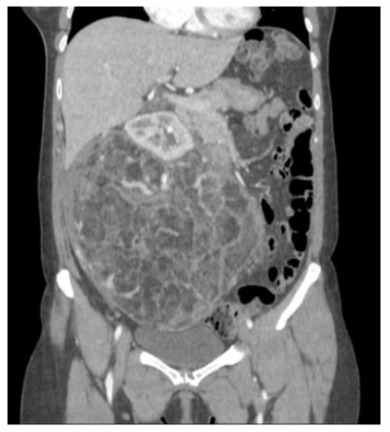

Patient A arrived at the Emergency department after experiencing two episodes of presyncope, which were accompanied by severe abdominal pain. A physical examination revealed a palpable abdominal tumor. The abdominal x-ray showed a large mass that had displaced the bowel (figure 1). Additionally, a CT scan showed findings compatible with Wunderlich syndrome, but there was no evidence of active bleeding (figure 2).

Figure 2: CT scan of patient A shows an AML with a maximum diameter of 24,5cm.